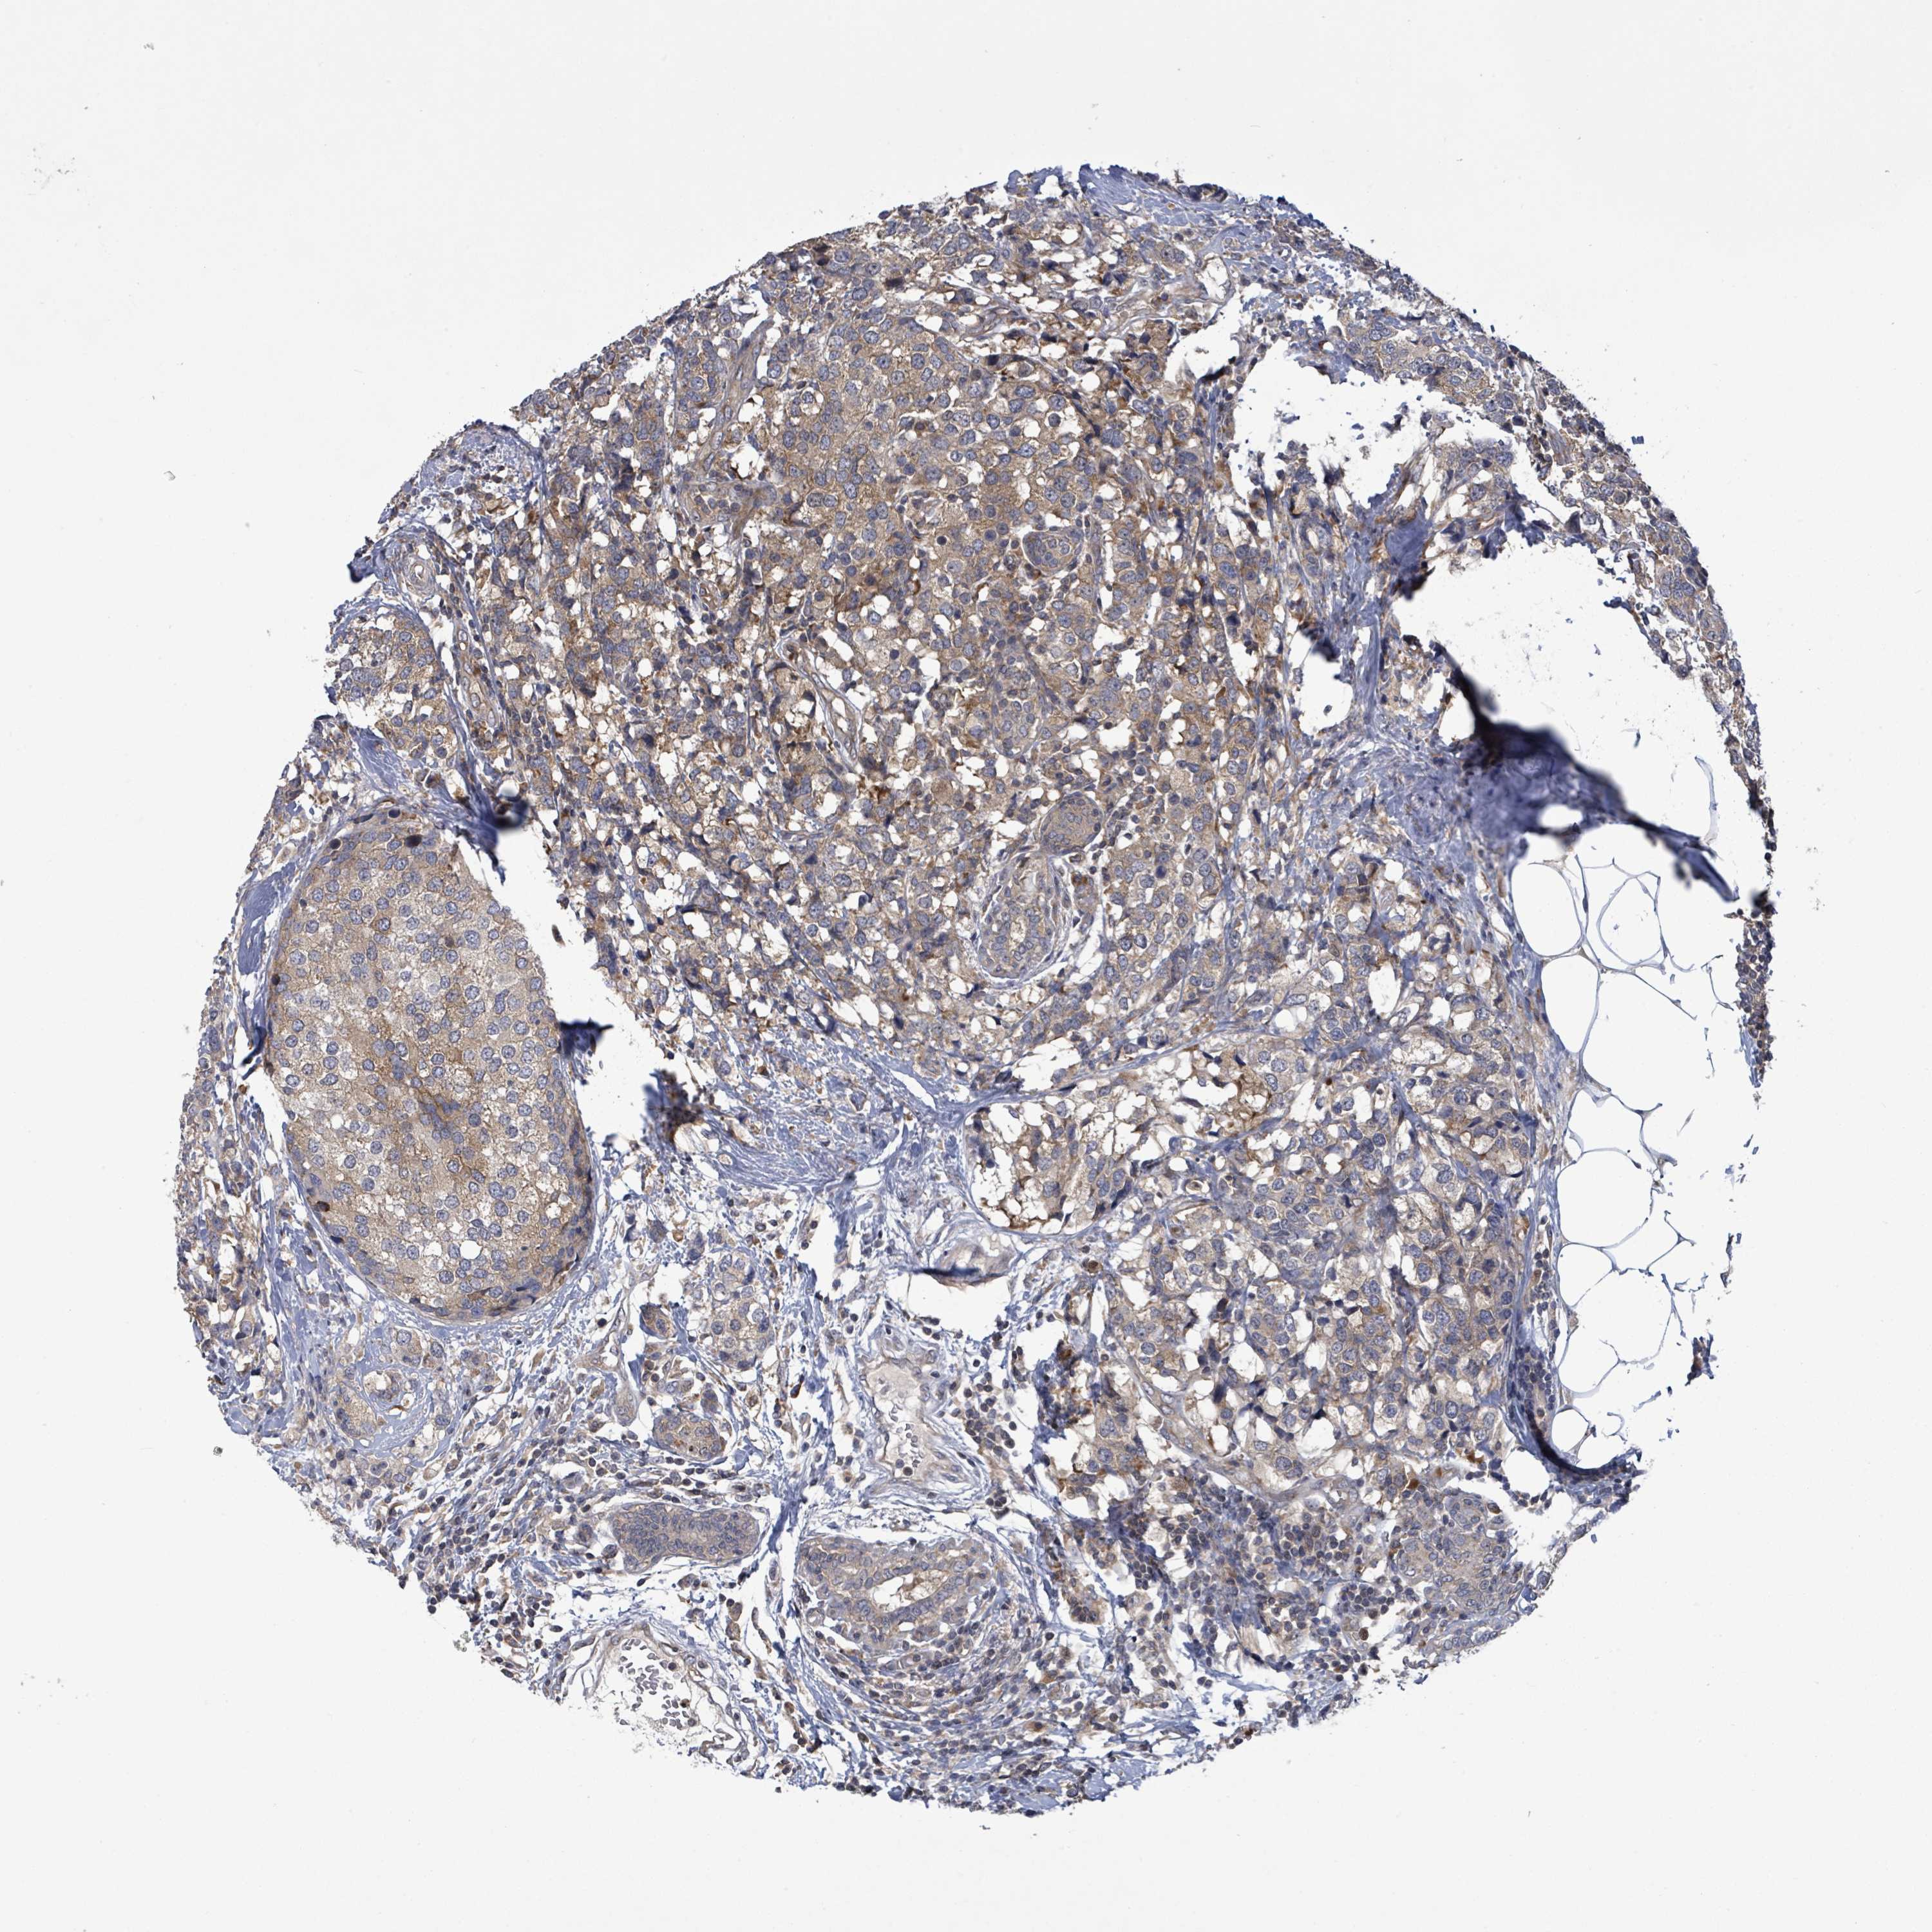

CANCER BREAST CANCER Show tissue menu

BRCA TCGA BRCA VALIDATION PROTEIN EXPRESSION

ANTIBODIES

AND

VALIDATION